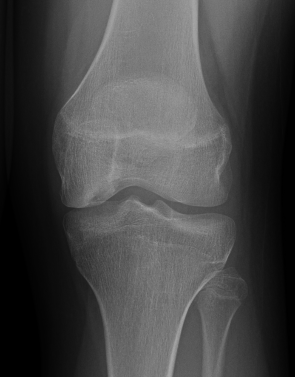

Xray

Intercondylar view / notch / tunnel view imperative

- most commonly seen in this view

- can miss the lesion unless have flexed knee view 30-50o

Xray classification

Stage 1: Normal / abnormal MRI

Stage 2: Lucent area of subchondral bone, can have surrounding sclerosis

Stage 3: Partial loosening

Stage 4: Completely detached / loose body

Type 2 Type 3 Type 3